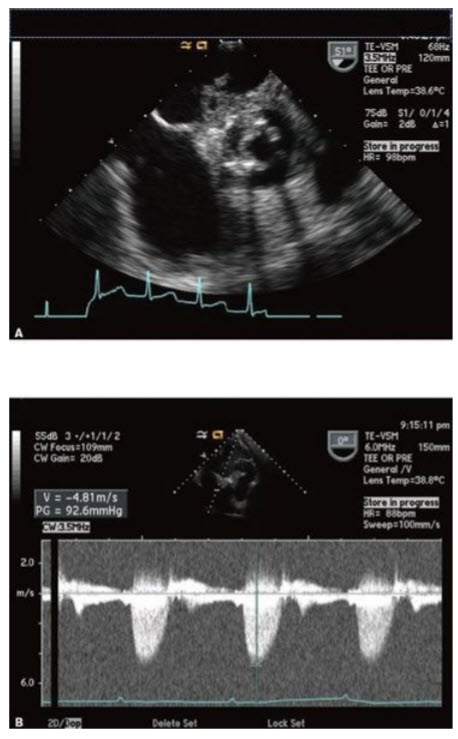

The patient is a 70-year-old woman with a history of hypertension, but no prior cardiac history, who comes in with sudden onset of CP, which later migrates to her back. She is diagnosed with a computed tomography (CT) of her chest to have a type I aortic dissection. Her blood pressure is 100/70 mmHg and her heart rate is 115 bpm. Images from her TTE are in Figures below A–C.

A. Apical four-chamber view (TTE). B. M-mode through the IVC in the subcostal view (TTE). C. Continuous-wave Doppler through the mitral valve showing mitral valve inflow pattern.

The next step in her care would be

Emergent cardiac surgery. The images demonstrate a patient with cardiac tamponade. Findings include significant respiratory variation of MV inflows (>25%) and RV diastolic collapse, RA inversion, and inferior vena cava plethora (dilated >2 cm and does not collapse normally with inspiration). A patient with a type I dissection and cardiac tamponade needs to go to emergent cardiac surgery as soon as possible for drainage of the pericardium and repair of the aorta. Pericardiocentesis could potentially cause complete rupture of the flap into the pericardium, causing cardiac arrest and death. An aortic stent graft is currently not the treatment of choice for a type I dissection and could certainly not address the problem of tamponade. Coronary angiography in this patient would only delay the definitive therapy (surgery) as well as possibly further propagate the dissection flap. Recall that delay of surgery in a patient with a type I dissection is associated with a 1% per hour increase in mortality in the first 48 hours of the process. (Note that this patient has not had prior cardiac surgery—if the person had prior cardiac surgery, that would likely change the need for cardiac catheterization prior to surgery, although in this patient emergent surgical drainage of the pericardium would be needed.)